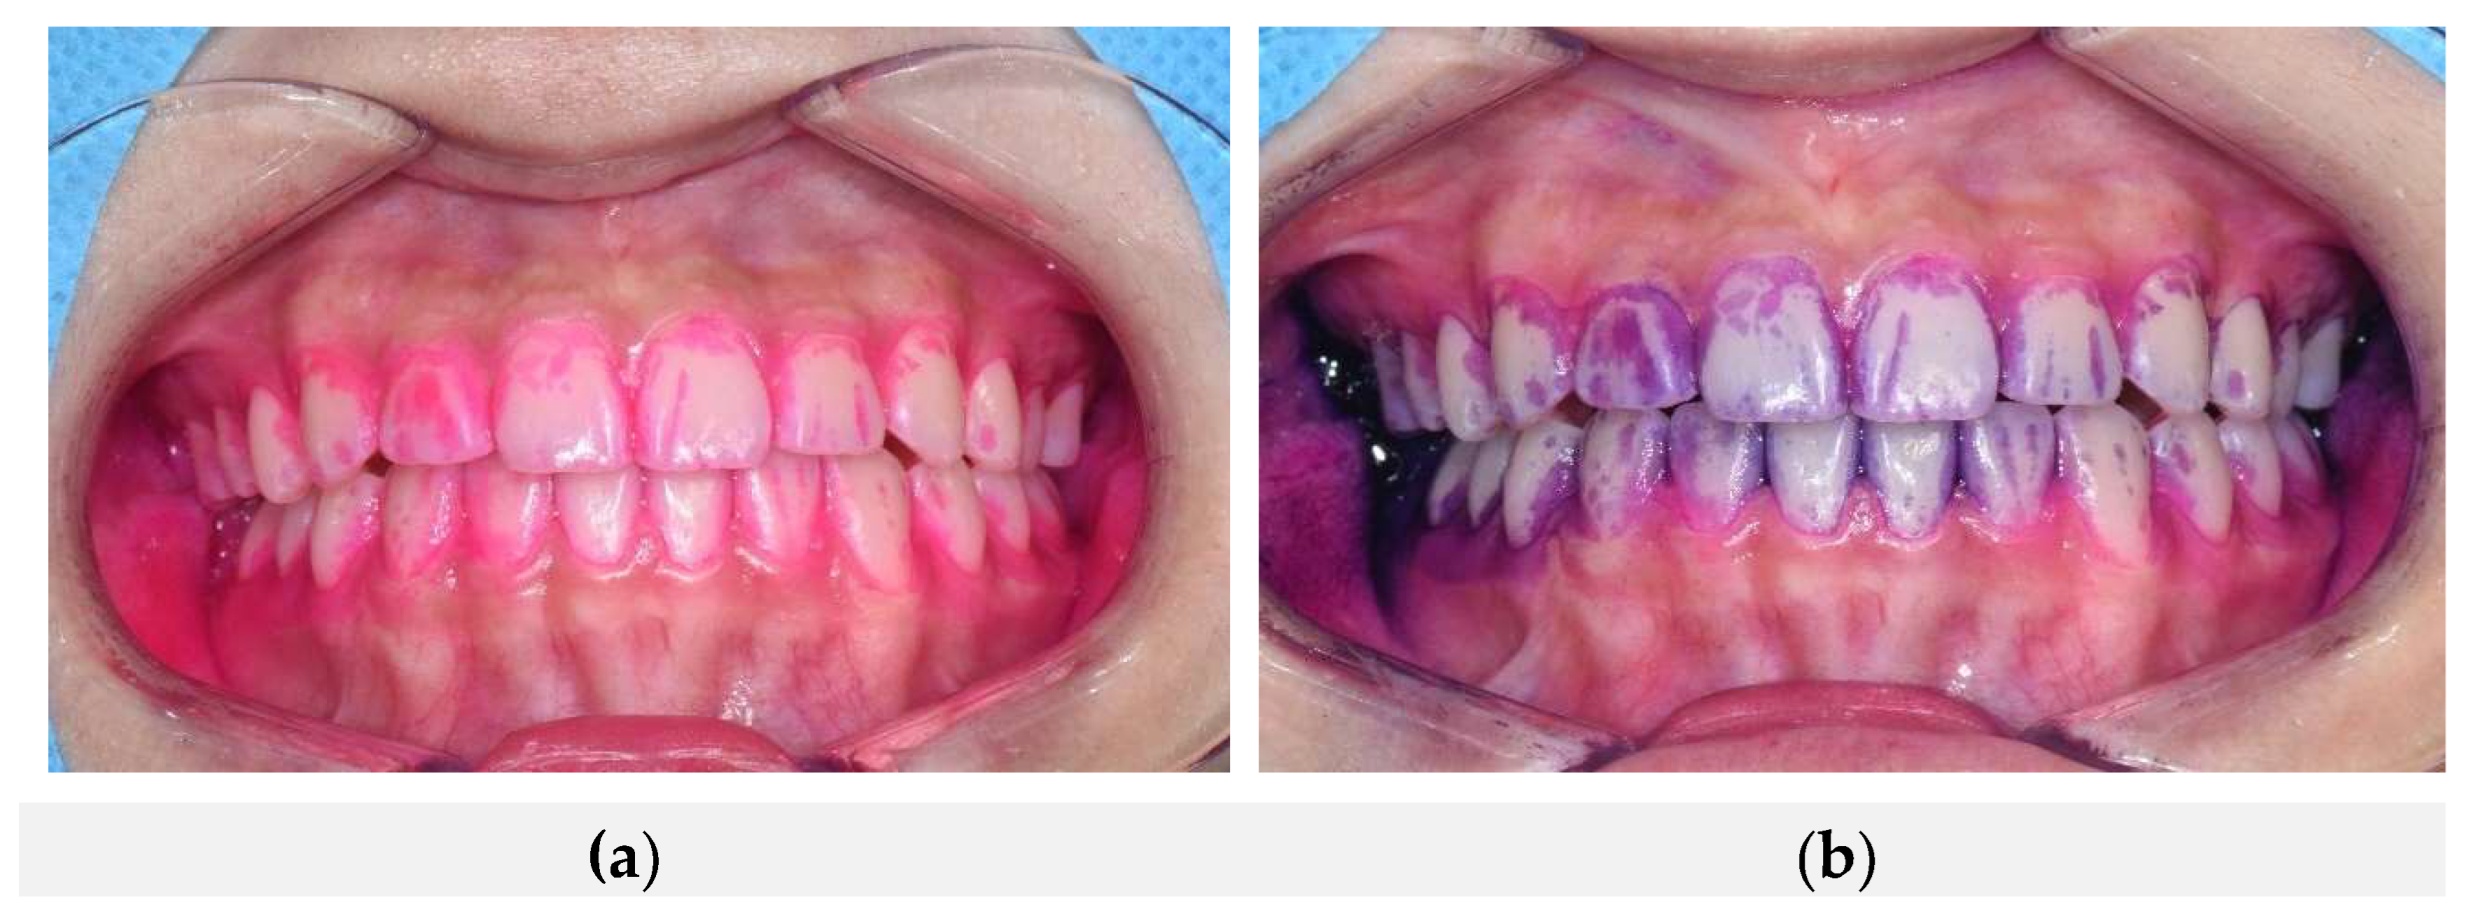

Figure 2 shows the plaque staining results after sequential application of the natural dye-based disclosing agent followed by the conventional dye-based disclosing agent. Both agents consistently stained identical regions of dental plaque, including buccal surfaces of the maxillary and mandibular anterior teeth, gingival margins, and proximal (mesial and distal) areas, demonstrating complete overlap in staining patterns. These results suggest that both dye-based agents accurately detect the same plaque locations regardless of application order. Thus, these findings qualitatively confirm that the natural dye-based disclosing agent possesses equivalent clinical efficacy compared to the conventional product in terms of spatial accuracy and reproducibility of plaque staining.

Figure 2. Concordance of plaque staining following sequential application of two different dye-based plaque disclosing agents. (a) Plaque staining observed after application of the natural dye-based disclosing agent; (b) Plaque staining observed after subsequent application of the conventional dye-based disclosing agent. Both agents consistently stained the same regions of dental plaque, demonstrating a high degree of spatial concordance.